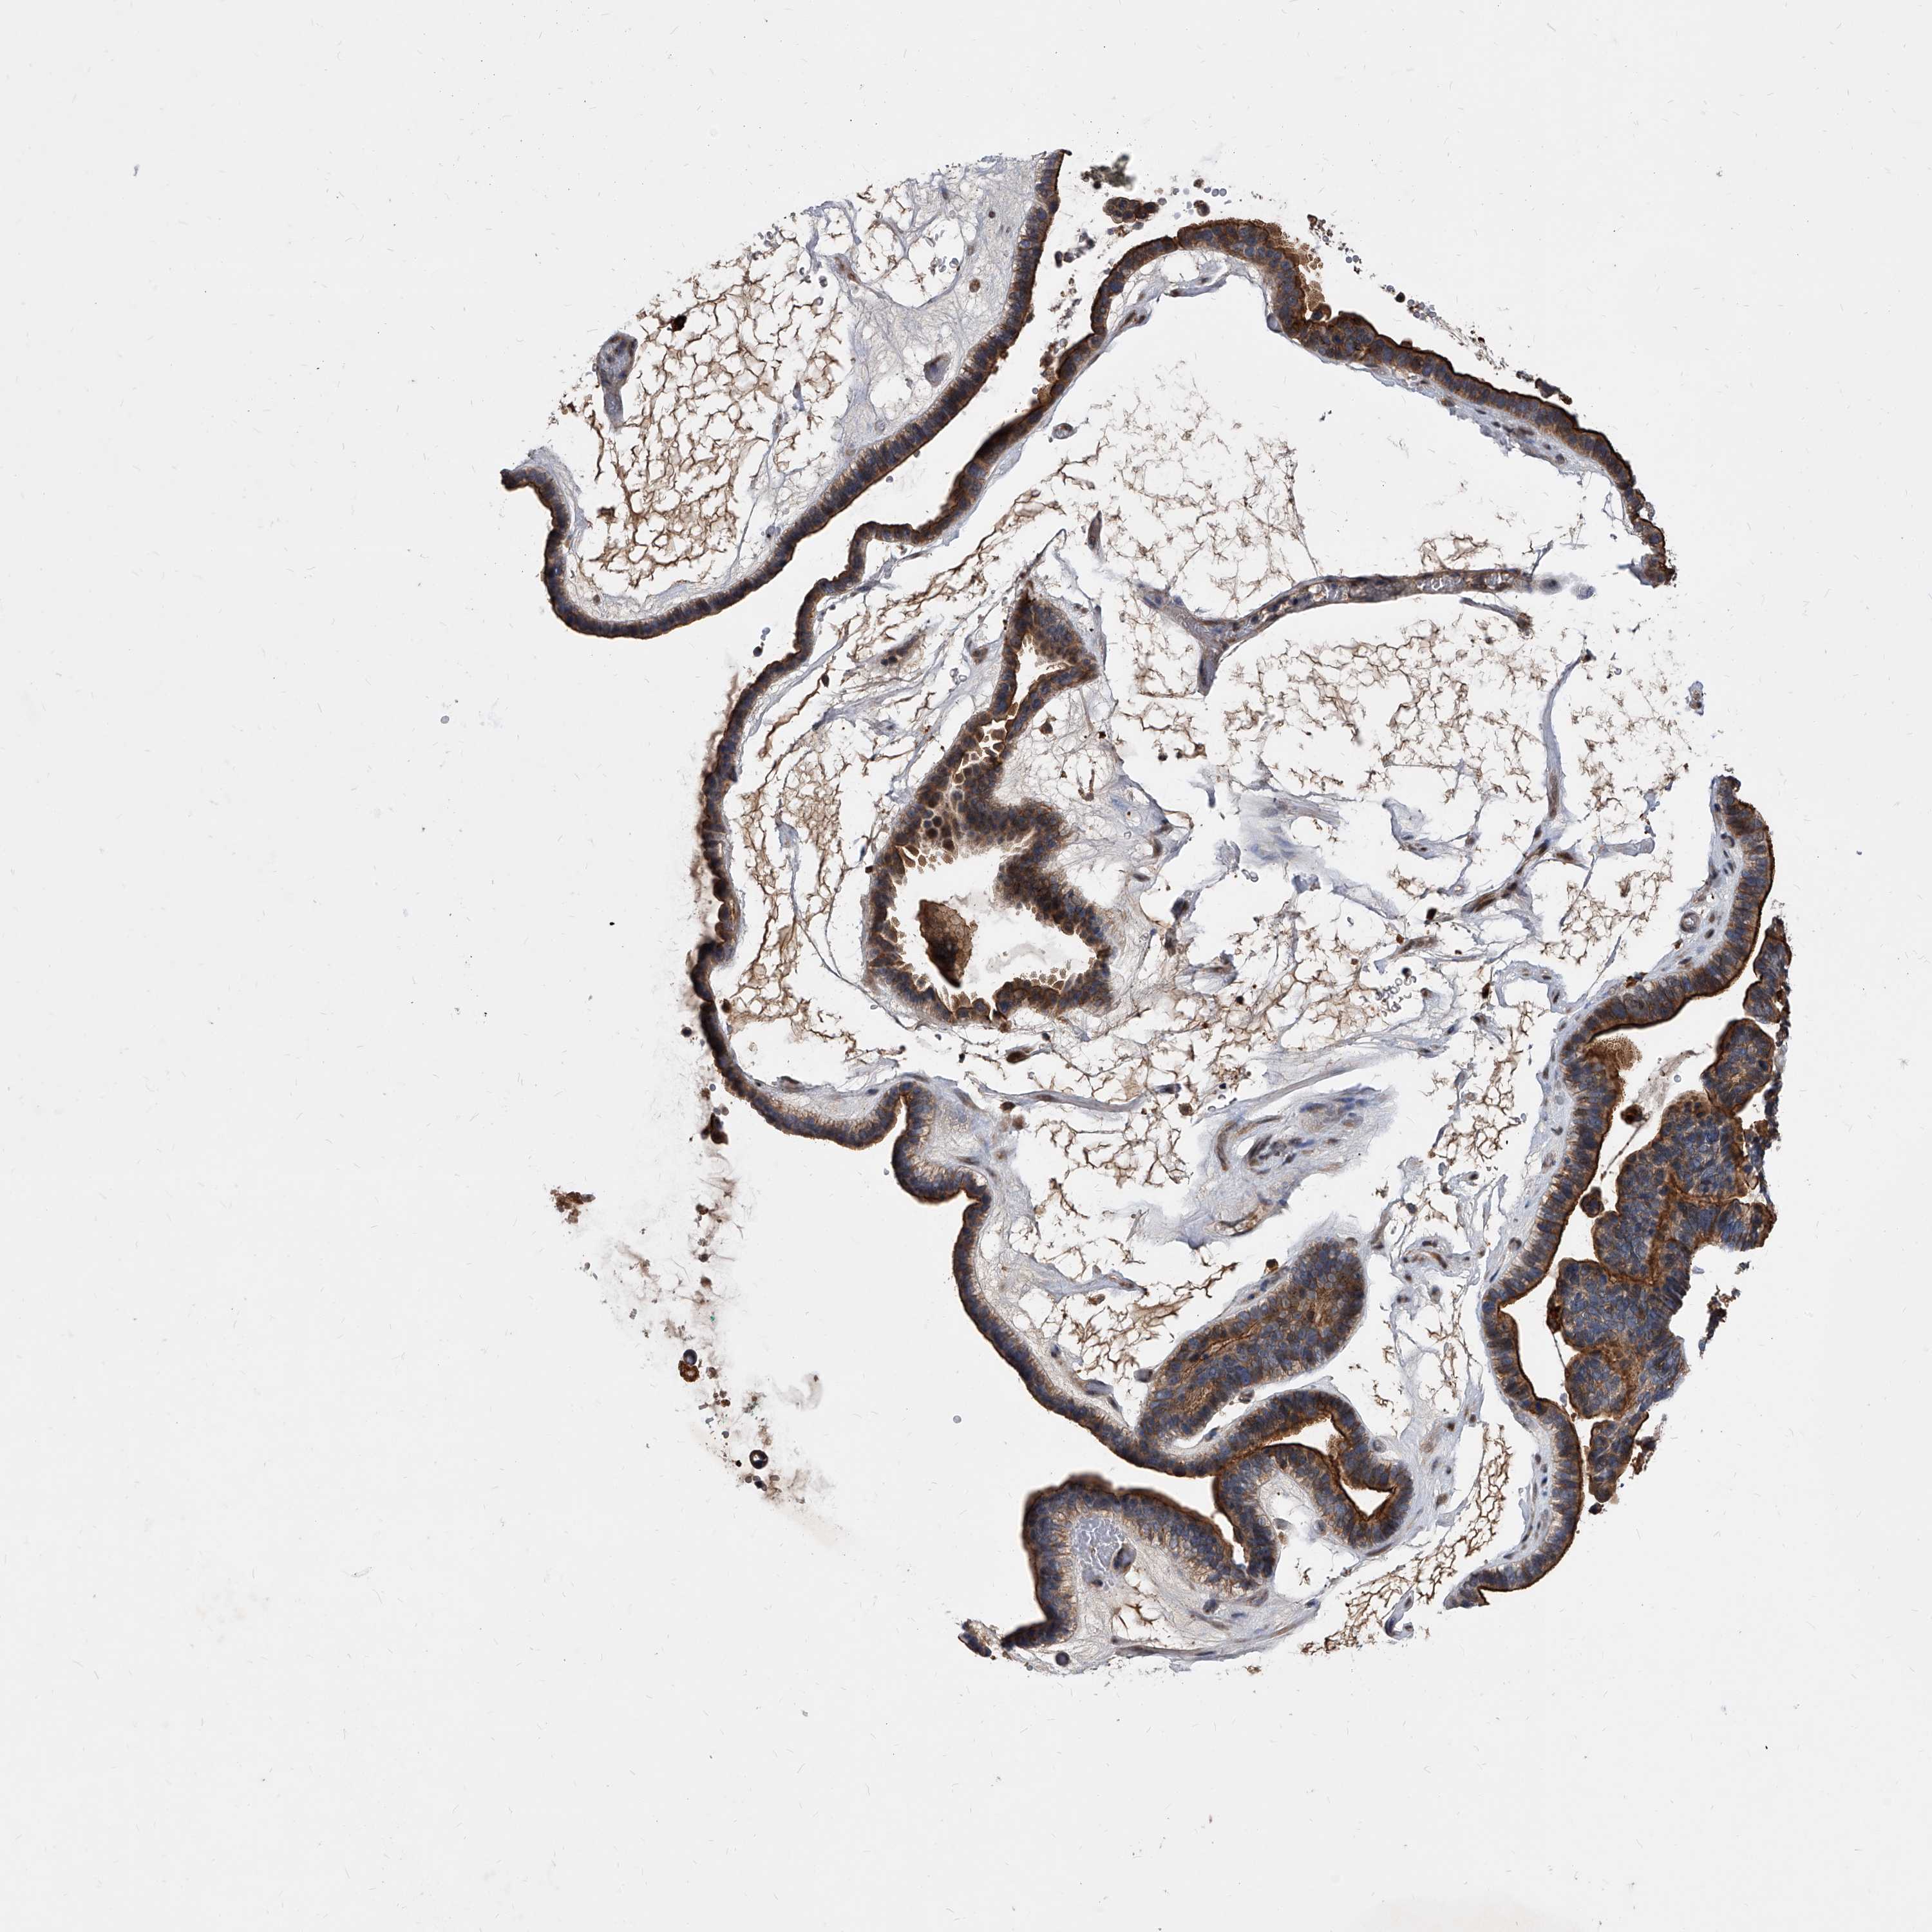

OVARIAN CANCER - Protein expressioni

A mouse-over function shows sample information and annotation data. Click on an image to view it in a full screen mode. Samples can be filtered based on level of antibody staining by selecting one or several of the following categories: high, medium, low and not detected. The assay and annotation is described here.

Note that samples used for immunohistochemistry by the Human Protein Atlas do not correspond to samples in the TCGA dataset.

Antibody stainingi

Antibody staining in the annotated cell types in the current human tissue is reported as not detected, low, medium, or high, based on conventional immunohistochemistry profiling in selected tissues. This score is based on the combination of the staining intensity and fraction of stained cells.

Each image is clickable and will lead to virtual microscopy that enables deeper exploration of all samples and also displays staining intensity scores, fraction scores and subcellular localization as well as patient and tissue information for each sample.

Antibody HPA029242

Cystadenocarcinoma, serous, NOS

Carcinoma, endometroid

Cystadenocarcinoma, mucinous, NOS

Carcinoma, NOS